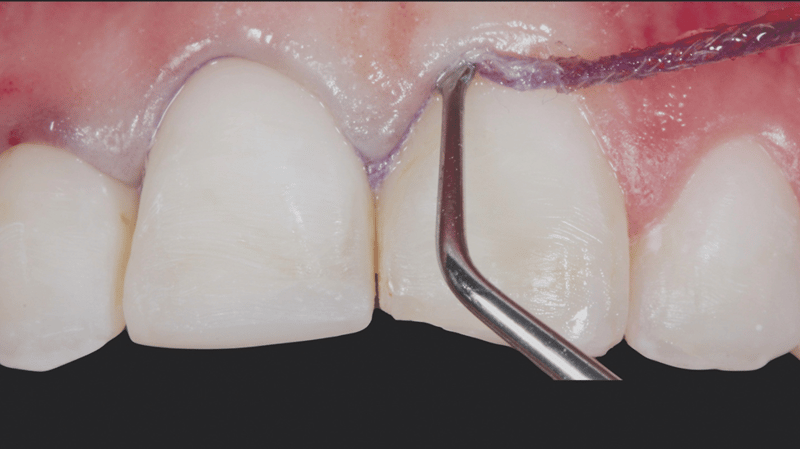

- Prepareren van de sulcus: Er werd een gebreide Ultrapak™-draad maat 0 in de sulcus aangebracht ter voorbereiding op het etsen.

- Etsen van onbeslepen glazuur: Er werd 30 seconden geëtst op het onbeslepen glazuur. Hiervoor werd Ultra-Etch met 35% fosforzuur gebruikt.

- Aanbrengen en uitblazen van adhesief: De adhesief Peak Universal Bond werd aangebracht en uitgeblazen door middel van perslucht en afzuiging.

- Cementeren: De veneers werden gecementeerd met behulp van de veneercement PermaShade™ LC in de kleur Translucent (niet beschikbaar in Europa).